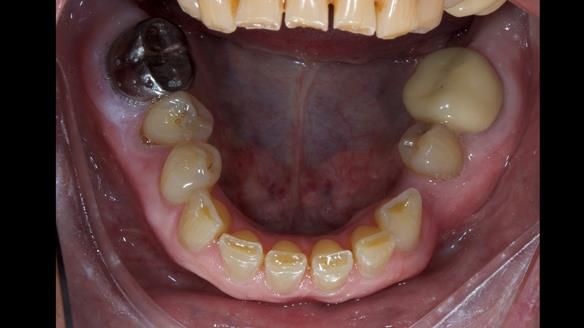

This is one of those cases that reminds me why I love removable prosthodontics. Pam was an absolute joy to treat — we were on the same page throughout. Her old upper flexible denture was loose, uncomfortable, and unaesthetic. We replaced it with a carefully designed metal-based upper partial denture/splint and new porcelain-bonded-to-zirconia (PBZ) crowns for the canines. The result is stable, comfortable, and natural-looking.

- Diagnosis and plan – Flexible upper denture ill-fitting with poor stability, retention, and appearance. Plan: metal-based upper partial denture/splint with lighter porcelain-bonded-to-zirconia crowns on UR3 and UL3.